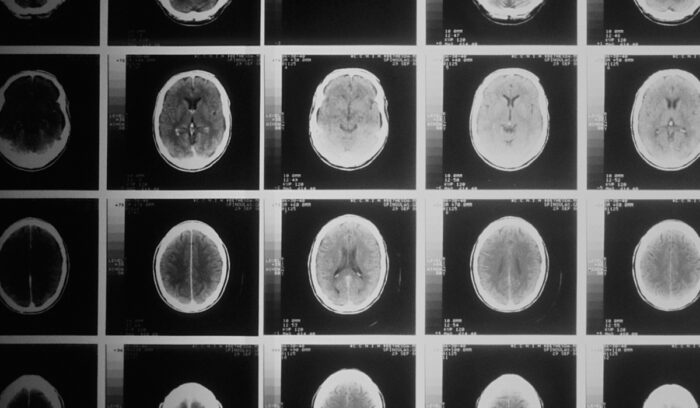

Scientists at Johns Hopkins University have developed a hydrogel that can be applied to the cavity in the brain left behind after a tumor is removed, slowly releasing medication to kill any cancer cells left behind.